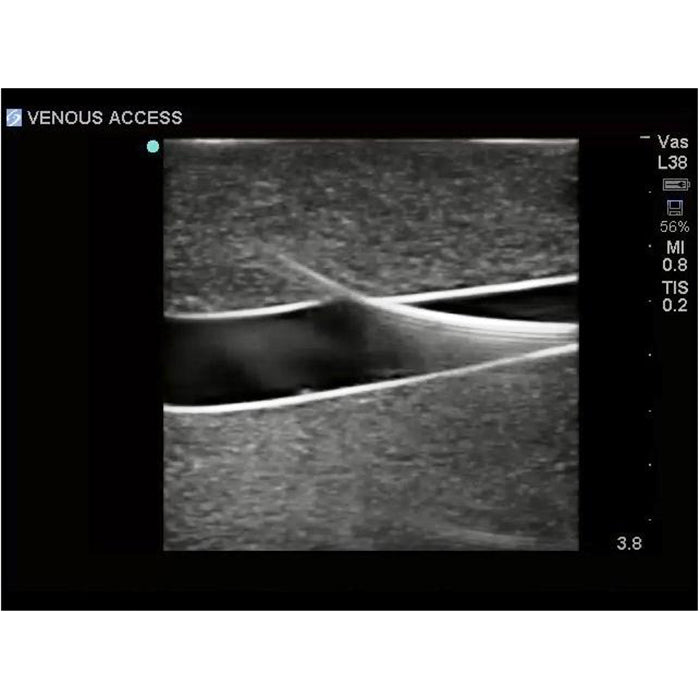

sternal notch. Users can utilize traditional anatomical landmarks for blind insertion techniques, or utilize ultrasound

Brand New! 2nd Generation upper torso ultrasound guided central line placement training model with transparent tissue insert allows users to develop and practice the skills necessary to gain proficiency in using ultrasound to guide central catheter insertions in the internal jugular vein (IJ), subclavian vein, and axillary vein while revealing the venous and arterial vessels as well as accessory boney structures. Developed with the goal of helping clinicians bridge the learning gap by allowing them to see the internal anatomical structures with their eyes as well as with ultrasound imaging, our transparent central line placement tissue offers superb ultrasound hands-on training. Using Blue Phantom proprietary simulated human tissue, this very realistic and ultra-durable transparent central venous access ultrasound training model is excellent for training clinicians in the psychomotor skills associated with ultrasound guided central line placement procedures. These ultrasound imaging skills include; using ultrasound system controls, transducer positioning and movement, recognition of arterial and venous anatomy, using ultrasound to target the appropriate vessels for cannulation, and performing a central venous access procedure.Helps

- Superb ultrasound imaging characteristics

- Accommodates full threading of guidewires and catheters

- Tissues match the acoustic characteristics of real human tissue so when you use your ultrasound system on our training models, you experience the same quality you expect from imaging patients in a clinical environment

- Superb ultrasound imaging characteristics

- Tissues match the acoustic characteristics of real human tissue so when you use your ultrasound system on our training models, you experience the same quality you expect from imaging patients in a clinical environment